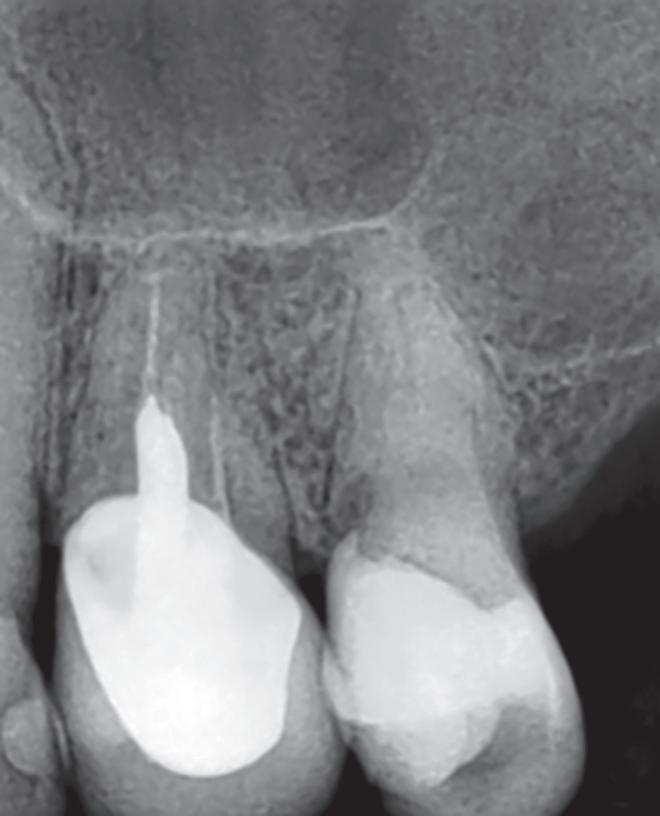

Fig. 19-1. Paciente idoso submetido a tratamento endodôntico (dente 25). (a) Canais atresiados (visualizados na radiografia periapical.) ( bliteração da entrada do canal vestibular. (d) Canal localizado e ampliado (uso de microscopia e ultrassom). ( a